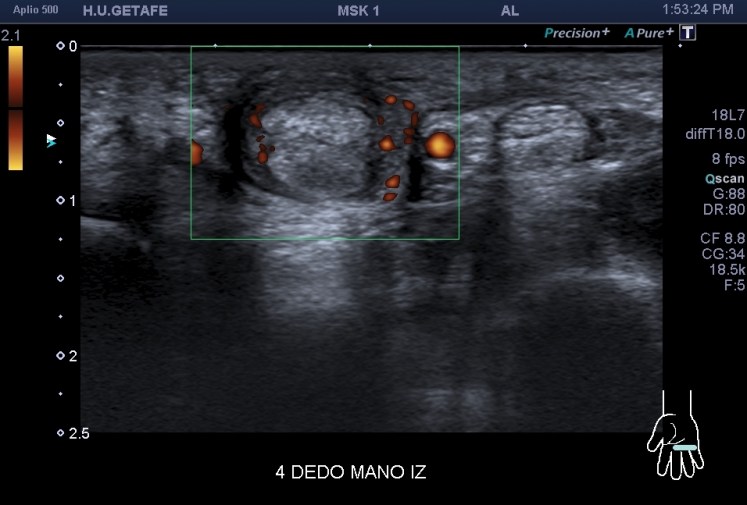

La imagen 4 y 5 reflejan la neovascularización asociada a algunos procesos como este. Igualmente preciosa.